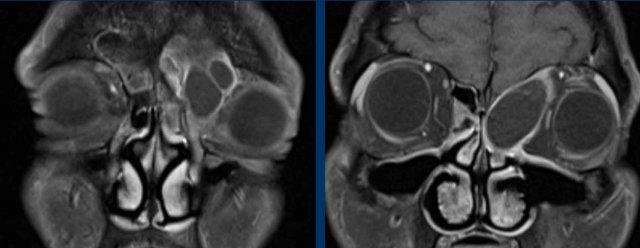

Tiếp tục với MRI…

Trên các hình ảnh STIR này, có thể thấy sự khác biệt về cường độ tín hiệu giữa xoang hàm và xoang sàng bị tắc nghẽn (mũi tên đen) và khối u (mũi tên trắng).

Ở bệnh nhân nang nhầy, toàn bộ tổn thương sẽ có cùng cường độ tín hiệu, khác với trường hợp này.

Trên hình ảnh khuếch tán, tổn thương có tín hiệu cao trên b1000.

Trên bản đồ ADC, tổn thương có tín hiệu rất thấp, thậm chí thấp hơn cả mô não, gợi ý tình trạng hạn chế khuếch tán rõ rệt.

Điều này có nghĩa là chúng ta đang đối mặt với một khối u tăng mật độ tế bào.

Đây là dấu hiệu cảnh báo thứ ba.